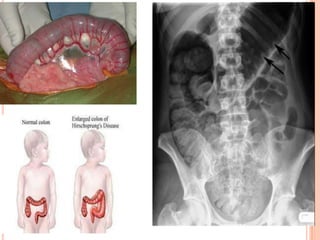

Intestino grueso hipertrofiado, alargado y dilatado de

manera crónica. Puede ser congénito o adquirido y

se relaciona con obstrucción mecánica o funcional

crónica.

Su valoración es con examen de colon y recto para

excluir obstrucción mecánica susceptible de

corrección por medios quirúrgicos.

 Congénito, enfermedad de Hirschsprung: falta de

migración de la célula de la cresta neural al

intestino grueso distal.

 Adquirido:    consecuencia       de   infeccion    o

estreñimiento cronico.

Intestino grueso hipertrofiado,alargado y dilatado de manera crónica. Puede ser congénito o adquirido y se relaciona con obstrucción mecánica o funcional crónica. Su valoración es con examen de colon y recto para excluir obstrucción mecánica susceptible de corrección por medios quirúrgicos.  Congénito, enfermedad de Hirschsprung: falta de migración de la célula de la cresta neural al intestino grueso distal.  Adquirido: consecuencia de infeccion o estreñimiento cronico.